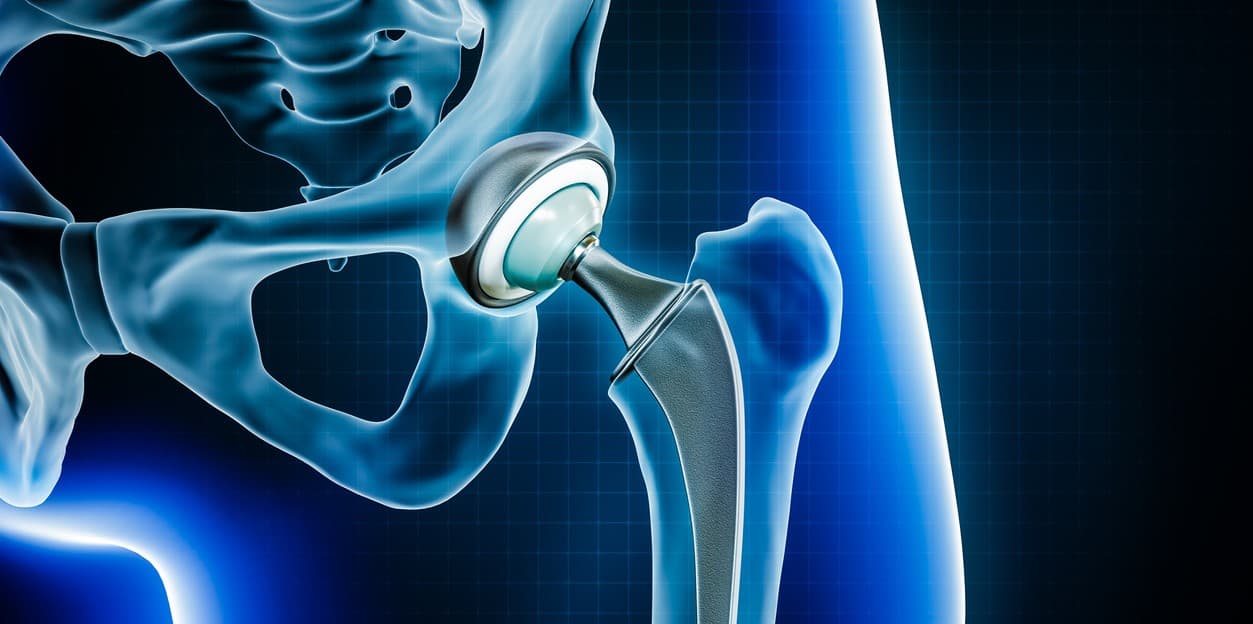

Choosing the best hip replacement implant depends on individual goals and biology rather than a universal winner. Modern implants combine a femoral stem, a ball (head), and an acetabular liner or cup, and are made from metal, ceramic, and high‑density polyethylene in various pairings to balance wear resistance, strength, and biocompatibility. For many patients metal‑on‑polyethylene and ceramic‑on‑polyethylene bearings offer a reliable mix of durability and low wear, making them common first‑line choices because they perform well across ages and activity levels. Ceramic‑on‑ceramic bearings have very low wear but carry a small risk of squeaking and are chosen selectively for younger, active patients who prioritize longevity. Hip resurfacing preserves more bone and can suit some younger men with good bone quality, but it has fallen out of favor for many because of specific metal‑related risks and fracture concerns. Fixation method—cemented, uncemented, or hybrid—is equally important: uncemented implants rely on bone ingrowth and are often preferred in younger patients with good bone, while cemented stems may be better for older patients with poor bone quality. Ultimately, the best implant is the one that matches your anatomy, lifestyle, and long‑term plan, chosen in partnership with an experienced surgeon.

Different types of hip replacement surgery offer tailored solutions—total, partial, resurfacing, and revision procedures, plus minimally invasive approaches—so the best option depends on the patient’s age, bone quality, activity goals, and the surgeon’s experience.